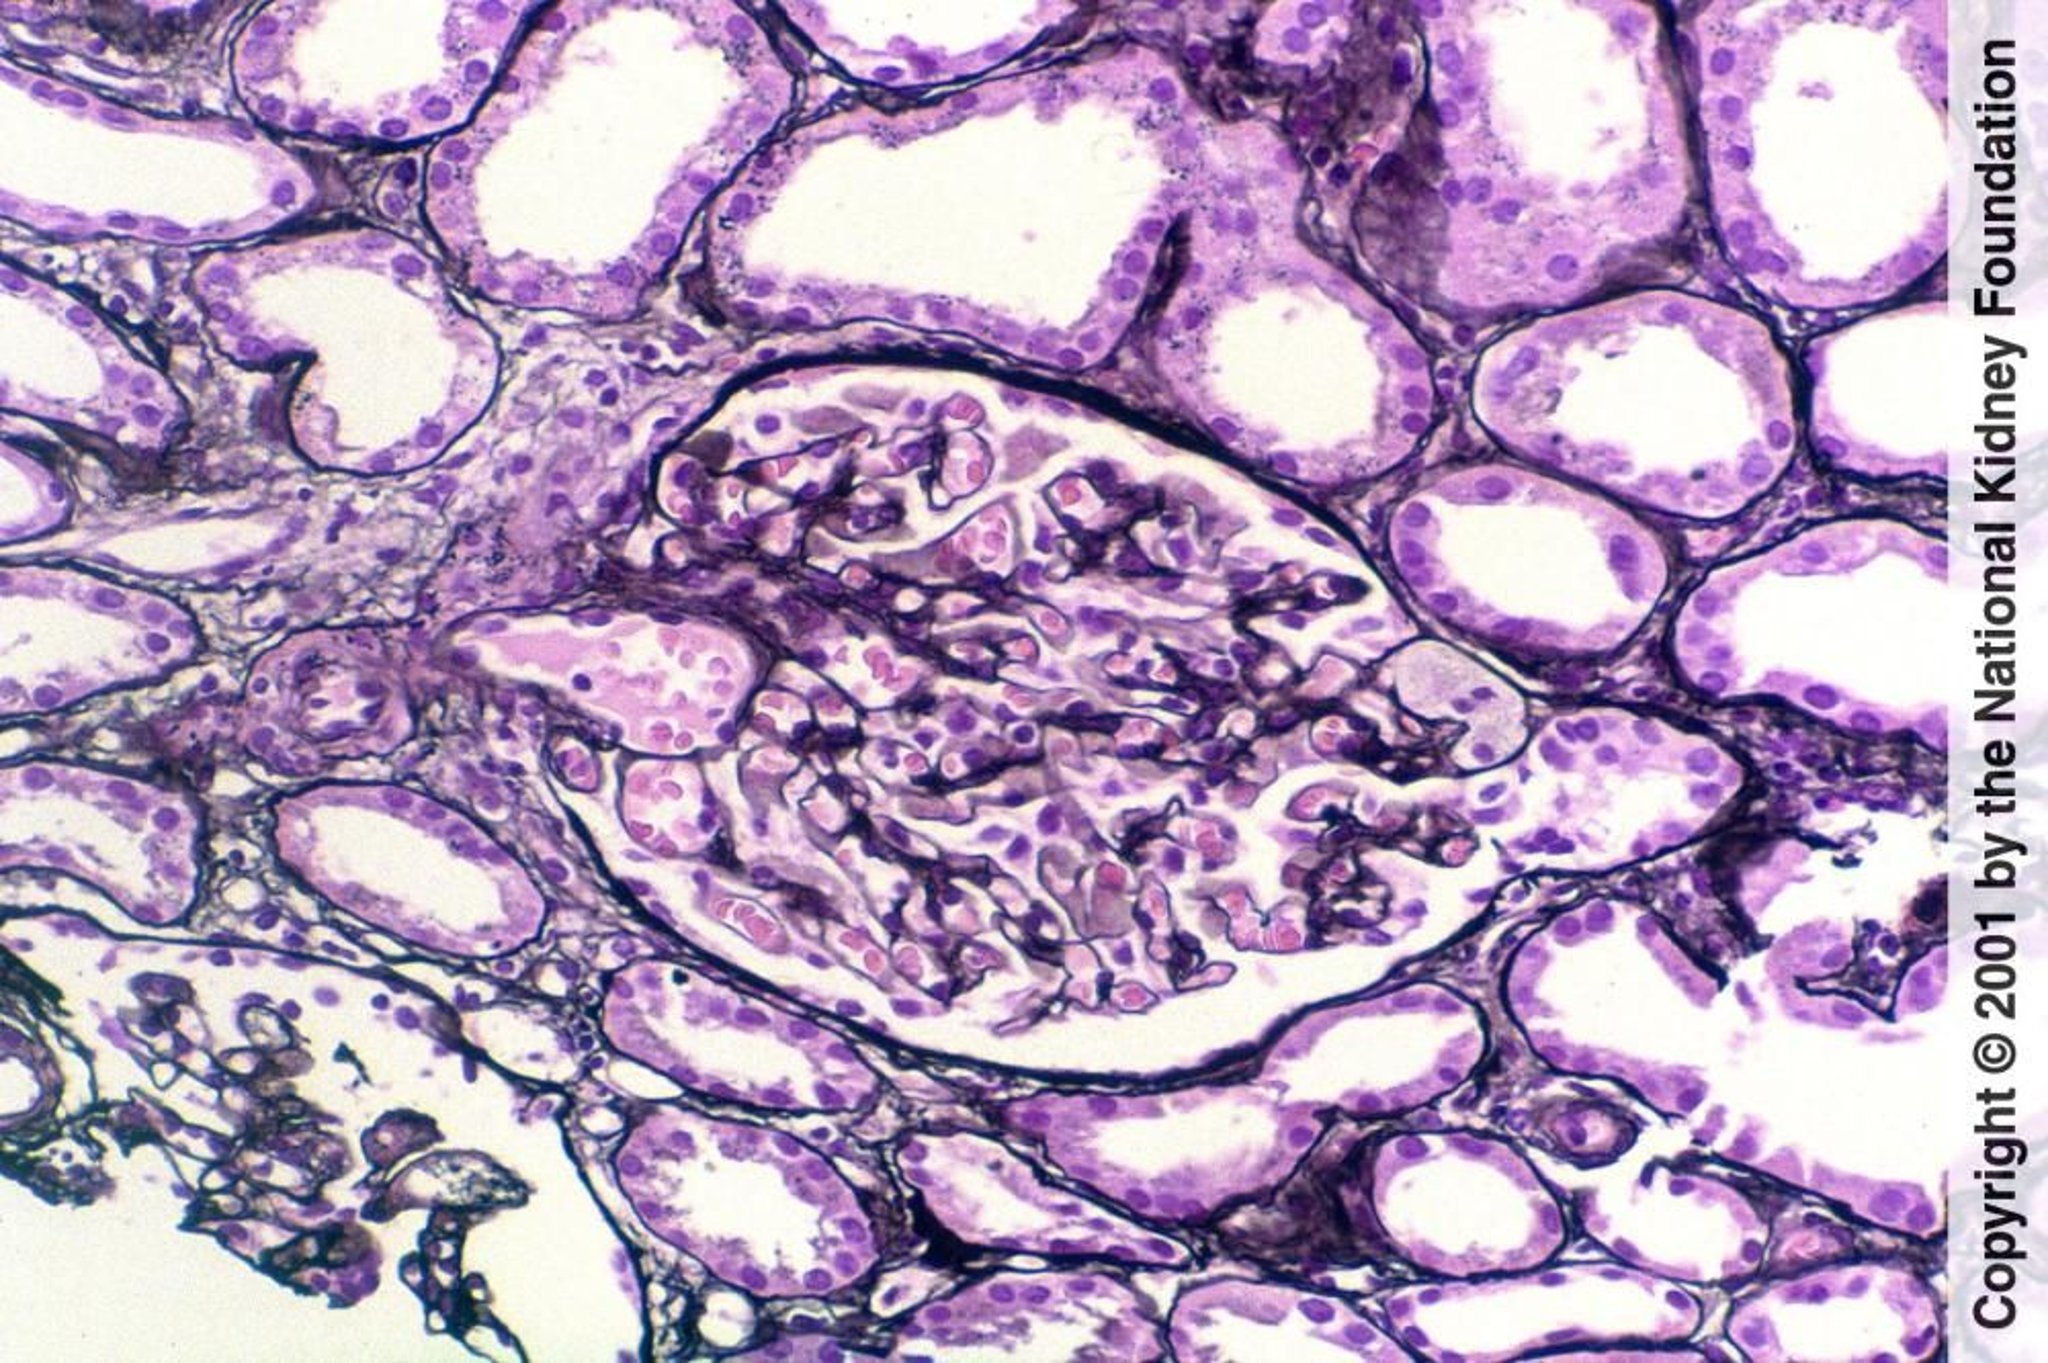

Glomerulosclerose segmentar e focal (lesão da ponta)

A lesão da ponta é a esclerose segmentar localizada no polo glomerular onde o túbulo se origina. Pode ser um marcador de melhor prognóstico (coloração prata de Jones, × 200).

Image provided by Agnes Fogo, MD, and the American Journal of Kidney Diseases' Atlas of Renal Pathology (see www.ajkd.org).